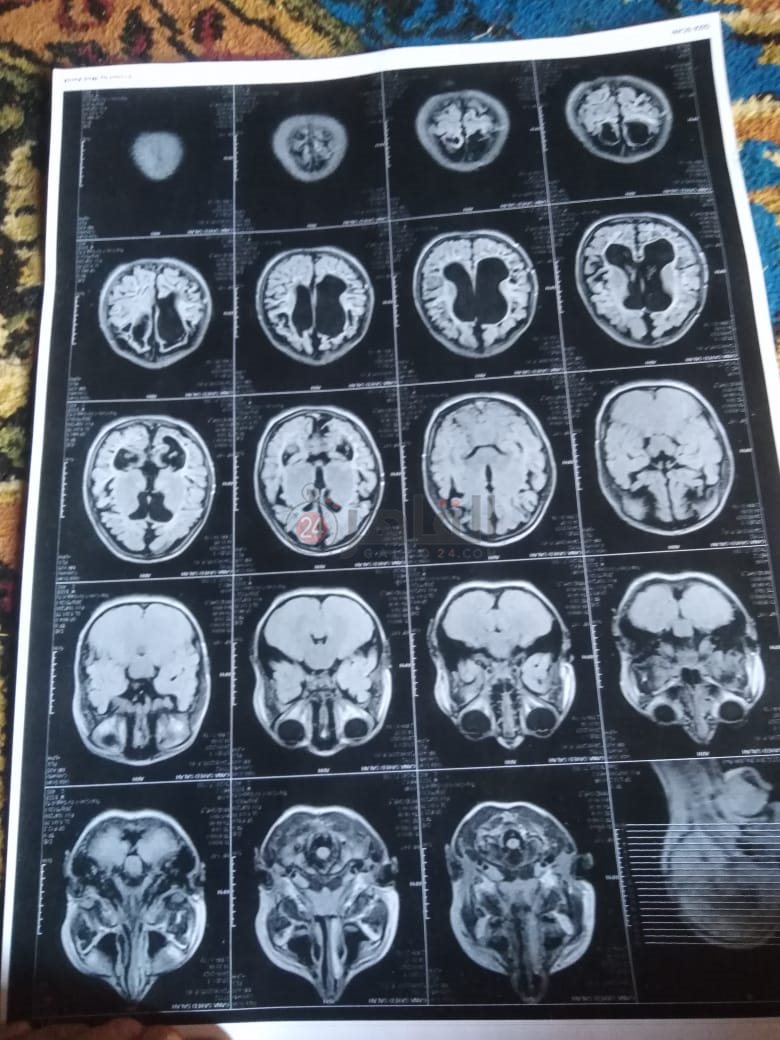

من جانبه، قال صلاح سيد، والد الطفلة جنى صلاح، إن ابنته تعاني من ضمور في المخ منذ ولادتها، نتيجة خطأ طبي، أدى إلى نقص كبير في الأكسجين لديها.

وأضاف في تصريحات خاصة لـ "القاهرة 24": "جنى تبلغ من العمر 6 سنوات، لا تستطيع المشي أو الوقوف على قدميها، نتيجة إصابتها بضمور في المخ منذ ولادتها".

وتابع: "مكنتش بتتحرك خالص، وجسمها طري، روحت كشفت عليها، وعملت أشعة وتحاليل كتير، أتأكدنا إصابتها بضمور في المخ"، مضيفًا:" مش بتعرف تأكل احنا اللي بنأكلها، هي عقلها كويس لكن مش بتتحرك ولا تتكلم".